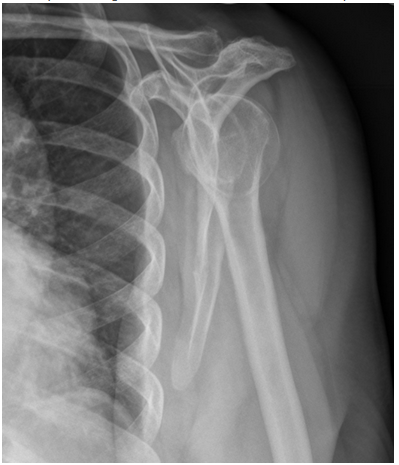

For the scapular Y lateral shoulder view, which adjustment should be made?

B - Adjust patient rotation to bring the humeral head closer to the ribs

For the scapular Y lateral shoulder view, an ideal radiograph demonstrates the true lateral of the scapula with the humeral head superimposed over the “Y” junction. In the image demonstrated, the patient is underrotated; this requires increased patient rotation to bring the humeral head closer to the ribs so that it sits within the “Y” of the acromion and coracoid. Decreasing patient rotation would bring the humeral head further away from the scapula.